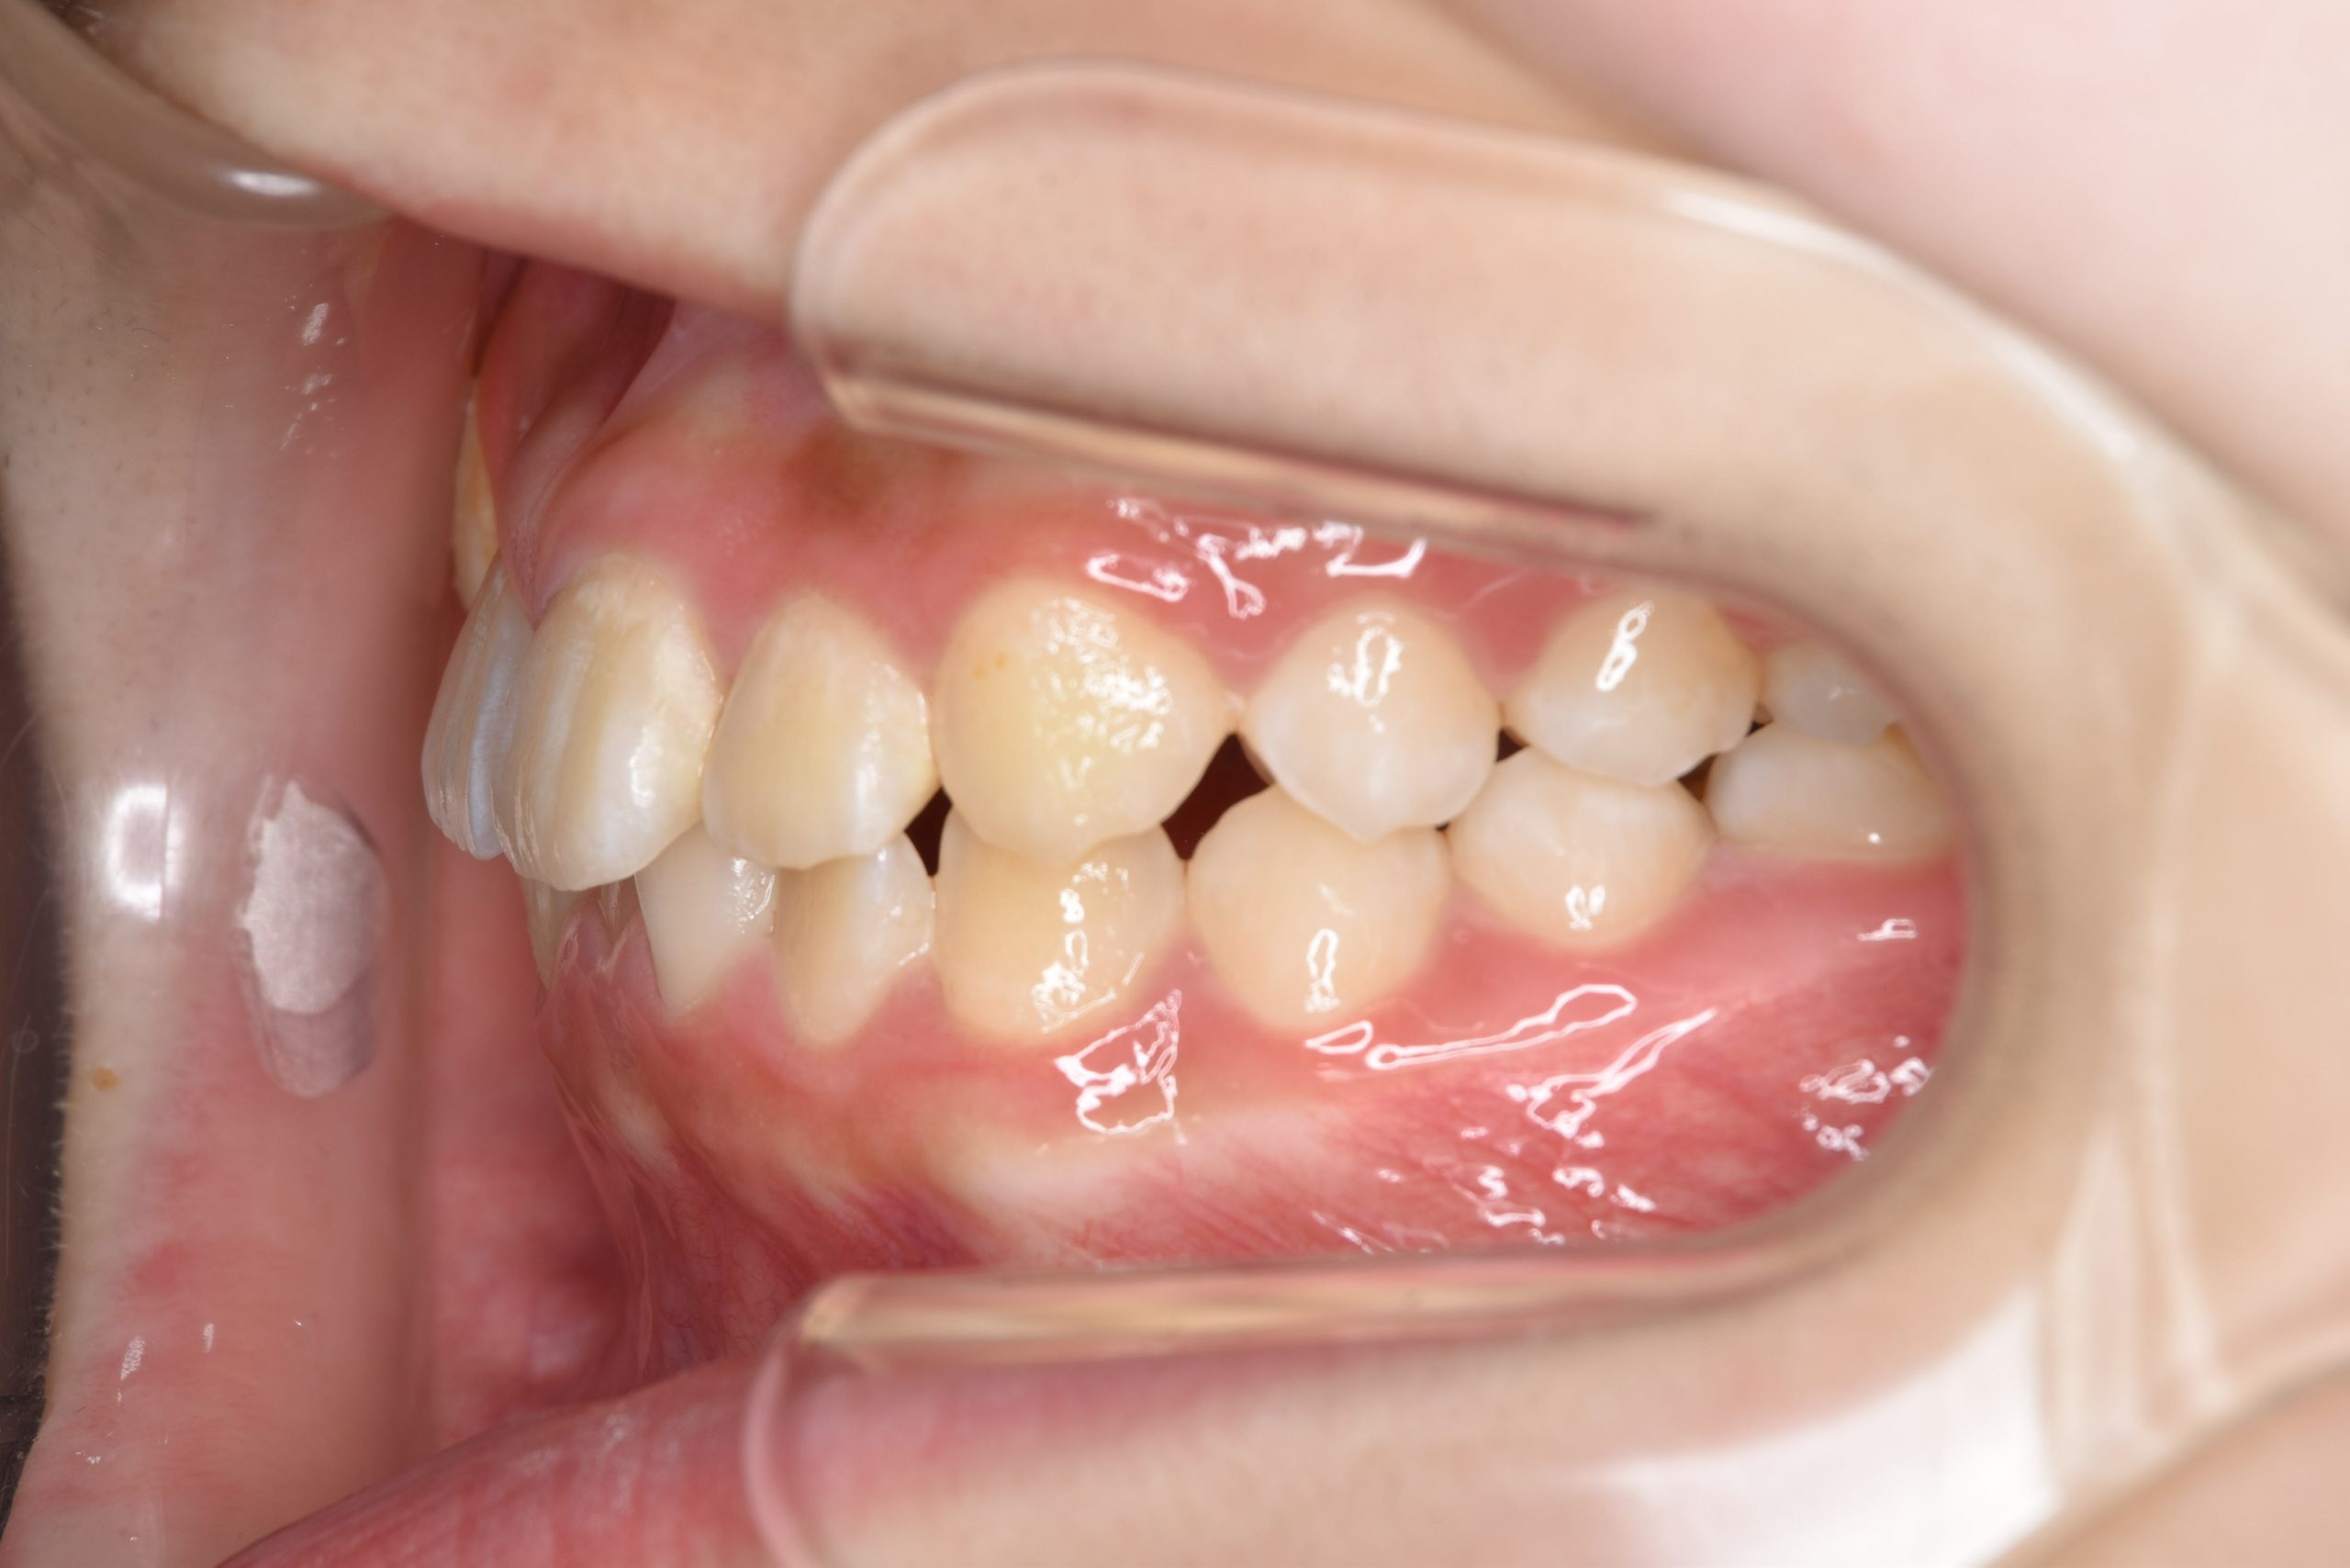

アフター

全顎ワイヤー矯正 症例_805

主訴 中心から前歯がずれている

施術内容 成人矯正1期治療

治癒期間 1年3か月間

費用 954,800円(税込)